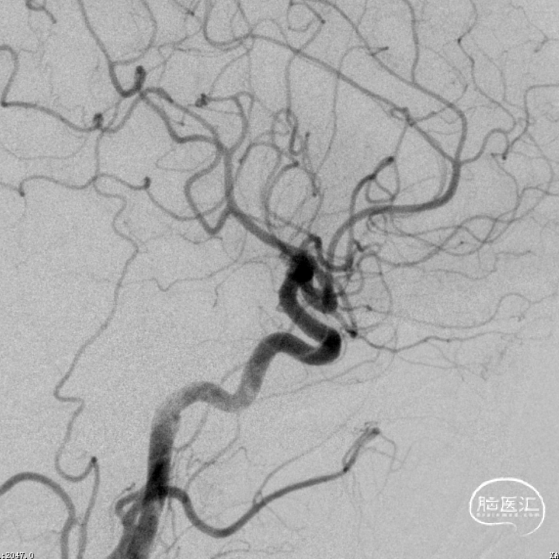

术前造影

患者推入放射科导管室平躺于检查床上,常规心电、血压监护;消毒右侧腹股沟区,铺手术巾,气管插管全身麻醉后,穿刺右侧股动脉,置入导管鞘,成功后置入超滑导丝及椎动脉导管,行左侧颈内动脉3D造影术,明确动脉瘤栓塞和辅助支架置入的工作体位。

载瘤动脉细小,经测量为0.87mm,角度为反向角度,释放支架易贴壁不良,颈内动脉段血管入路较迂曲,需要支撑力及柔顺性较好的微导管,同时避免微导管拉直血管并使血管位移而影响定位。